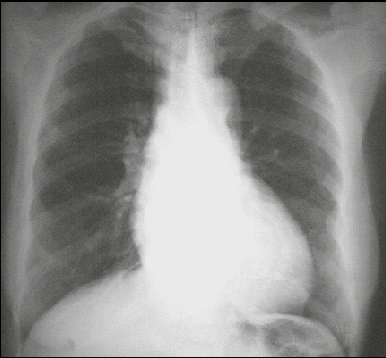

These chest X rays show left ventricular enlargement and a dilated aorta The PA view demonstrates cardiomegaly, as evidenced by a cardiothoracic ratio greater than 50%. Note also the increased inferolateral cardiac border that is consistent with ventricular enlargement due to volume overload. The ascending, transverse, and descending aortic shadows are also prominent.

The lateral view shows left ventricular enlargement, as evidenced by posterior displacement of the left ventricular shadow.